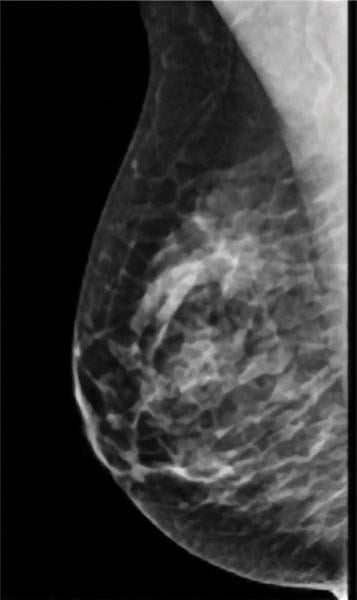

A comparision of a small breast cancer found in a patient without dense breast tissue (left), and a tumor found in a woman with dense fibroglandular tissue. For more information visit DenseBreast-info.org.

Roughly 40 percent of women of mammographic age (40 and older) fall into the last two categories, which are collectively considered dense. As density increases, it becomes more difficult to distinguish tumors and other masses from the surrounding tissue. Apart from this masking effect, dense breast tissue is itself a risk factor for developing breast cancer. Statistical evidence indicates that women with dense breasts are four to six times more likely to develop breast cancer than women with fatty tissue; they are also 17 times more likely to develop interval cancer (detected or presenting less than 12 months following a normal mammogram).